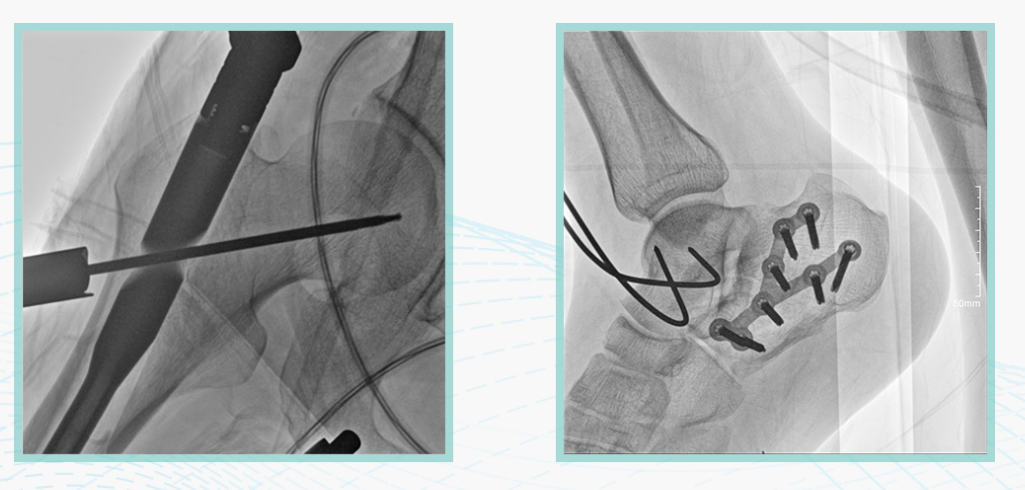

太阳成集团tyc122cc入口科技悦画移动C臂X线摄影系统,采用了业内技术最尖端的CMOS探测器。基于性能优异的针状CSI闪烁体涂层和高灵敏度的CMOS感光芯片,悦画可以实现在超低X线剂量条件下实现高清晰影像成像,相较于一般的影增移动C臂和平板C臂,动态范围更高,影像的层次感和对比度更好。

在产品的性能参数设计上,悦画的像素可达到200万,空间分辨率可达到3.2线对,采用16bit的影像灰度,悦画在影像后处理上,通过SPI金字塔图像算法,支持摄影、脉冲透视影像、连续透视等多种模式下的影像采集,动态透视影像视频支持保存与回放。双大屏的设计,透视影像支持三档放大,保证临床影像读取的便利。

悦画在影像的伪影处理上,也积累多项图像处理专利技术。通过对植入物的精准识别,悦画能够精准祛除植入物伪影与运动伪影,保证高质量的影像输出,无论是影像的对比度、分辨率(清晰度)相较于市面上的移动C臂产品都更胜一筹。